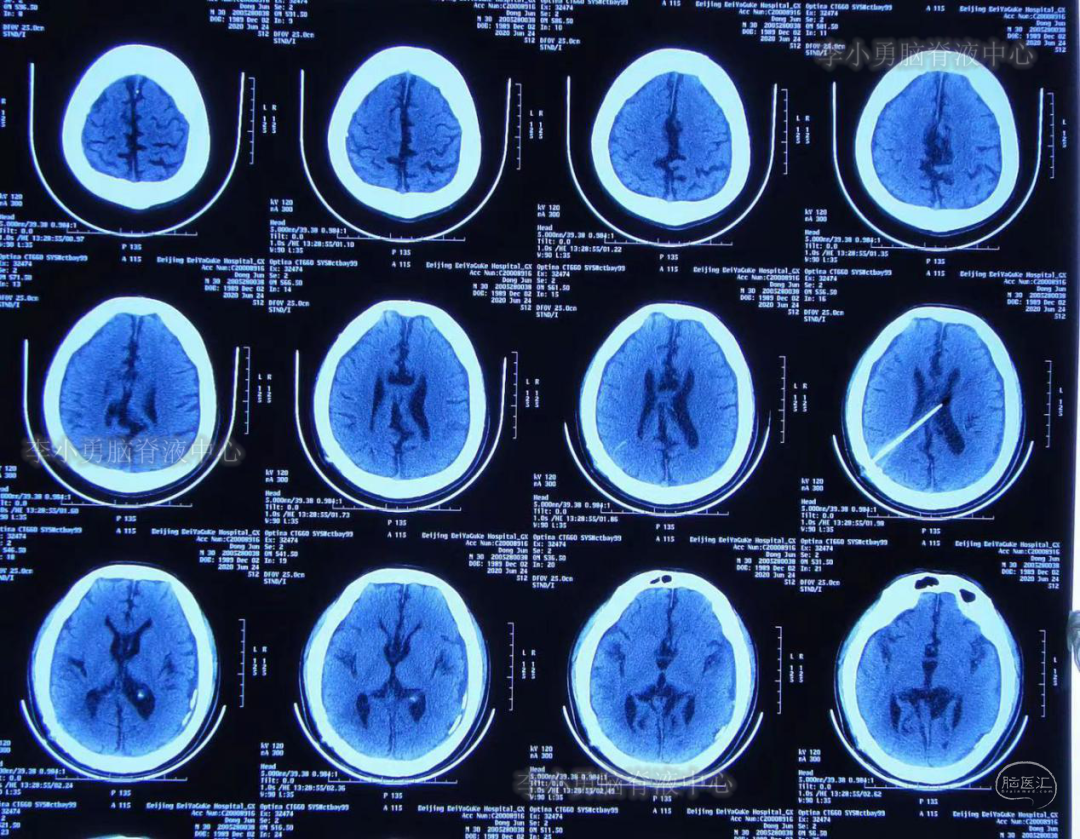

脑室外引流术后第23天即2020年6月24日,复查头部CT见脑室系统较前无明显变化(图-10),但从2020年6月5日-2020年6月24日18天内仅出现过3次头痛(注:术后5天时曾每2-3天头痛发作一次),且头痛程度较前明显减轻。

图-10:2020年6月24日头CT